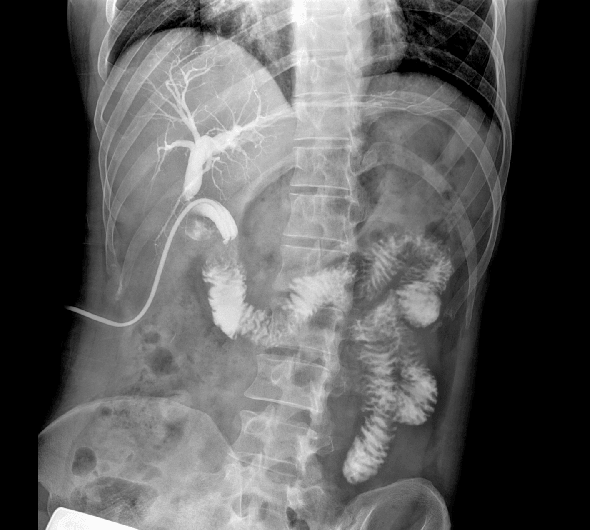

临床图像